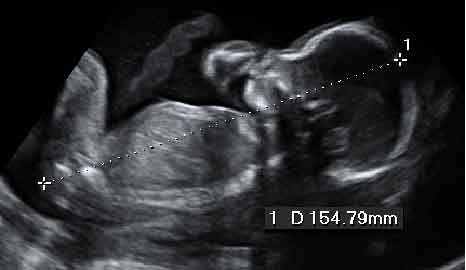

Ecografía 2D de la semana 20: Feto de perfil

En la semana 20 de embarazo, el feto ya mide 20 centímetros (desde la coronilla al coxis) y pesa alrededor de 250 gramos. La ecografía en 2D que se recomienda ahora se hace un estudio muy detallado de la morfología del bebé para descartar malformaciones y confirmar que su desarrollo es el correcto.

Ecografía 2D de un feto de 20 semanas de perfil

En este momento mide 20 centímetros de la cabeza a los pies.